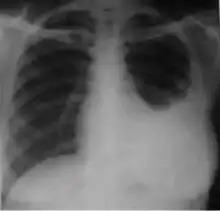

4. Pleural effusion - Presence of a significant amount of fluid within the pleural space. This finding must be distinguished from blunting of the costophrenic angle, which may or may not represent a small amount of fluid within the pleural space (except in children when even minor blunting must be considered a finding that can suggest active TB).